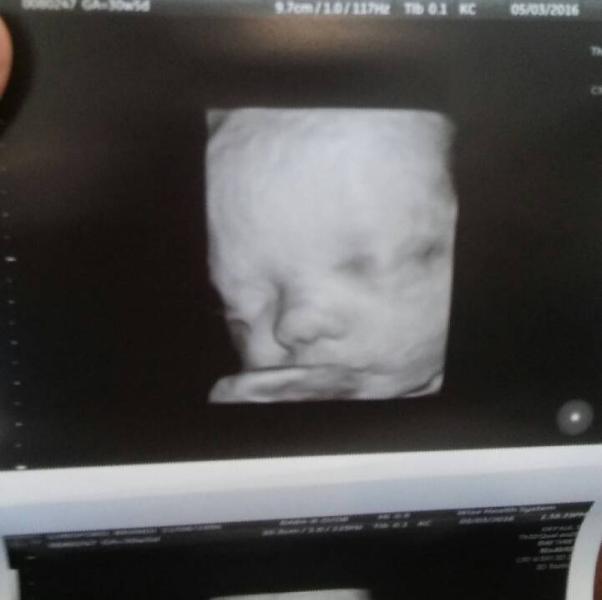

my baby girl is 3lb 7oz

03.05.2016